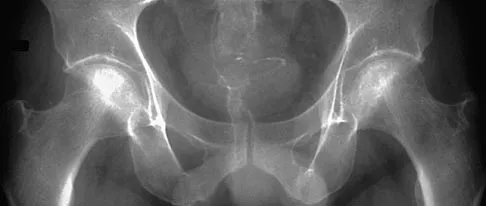

Which of the following choices best describes the fracture pattern shown in Figures 2a through 2c?

Explanation

The fracture pattern shown in the radiographs is a fracture of the posterior column. The only line interrupted on the AP pelvis is the ilioischial line. The obturator oblique view shows that the iliopectineal line is intact as is the outline of the posterior wall. The iliac oblique view shows an interruption of the ilioischial line and an intact anterior wall. Therefore, this fracture is a fracture of the posterior column. Letournel E, Judet R: Fractures of the Acetabulum, ed 2. Berlin, Germany, Springer Verlag, 1993.